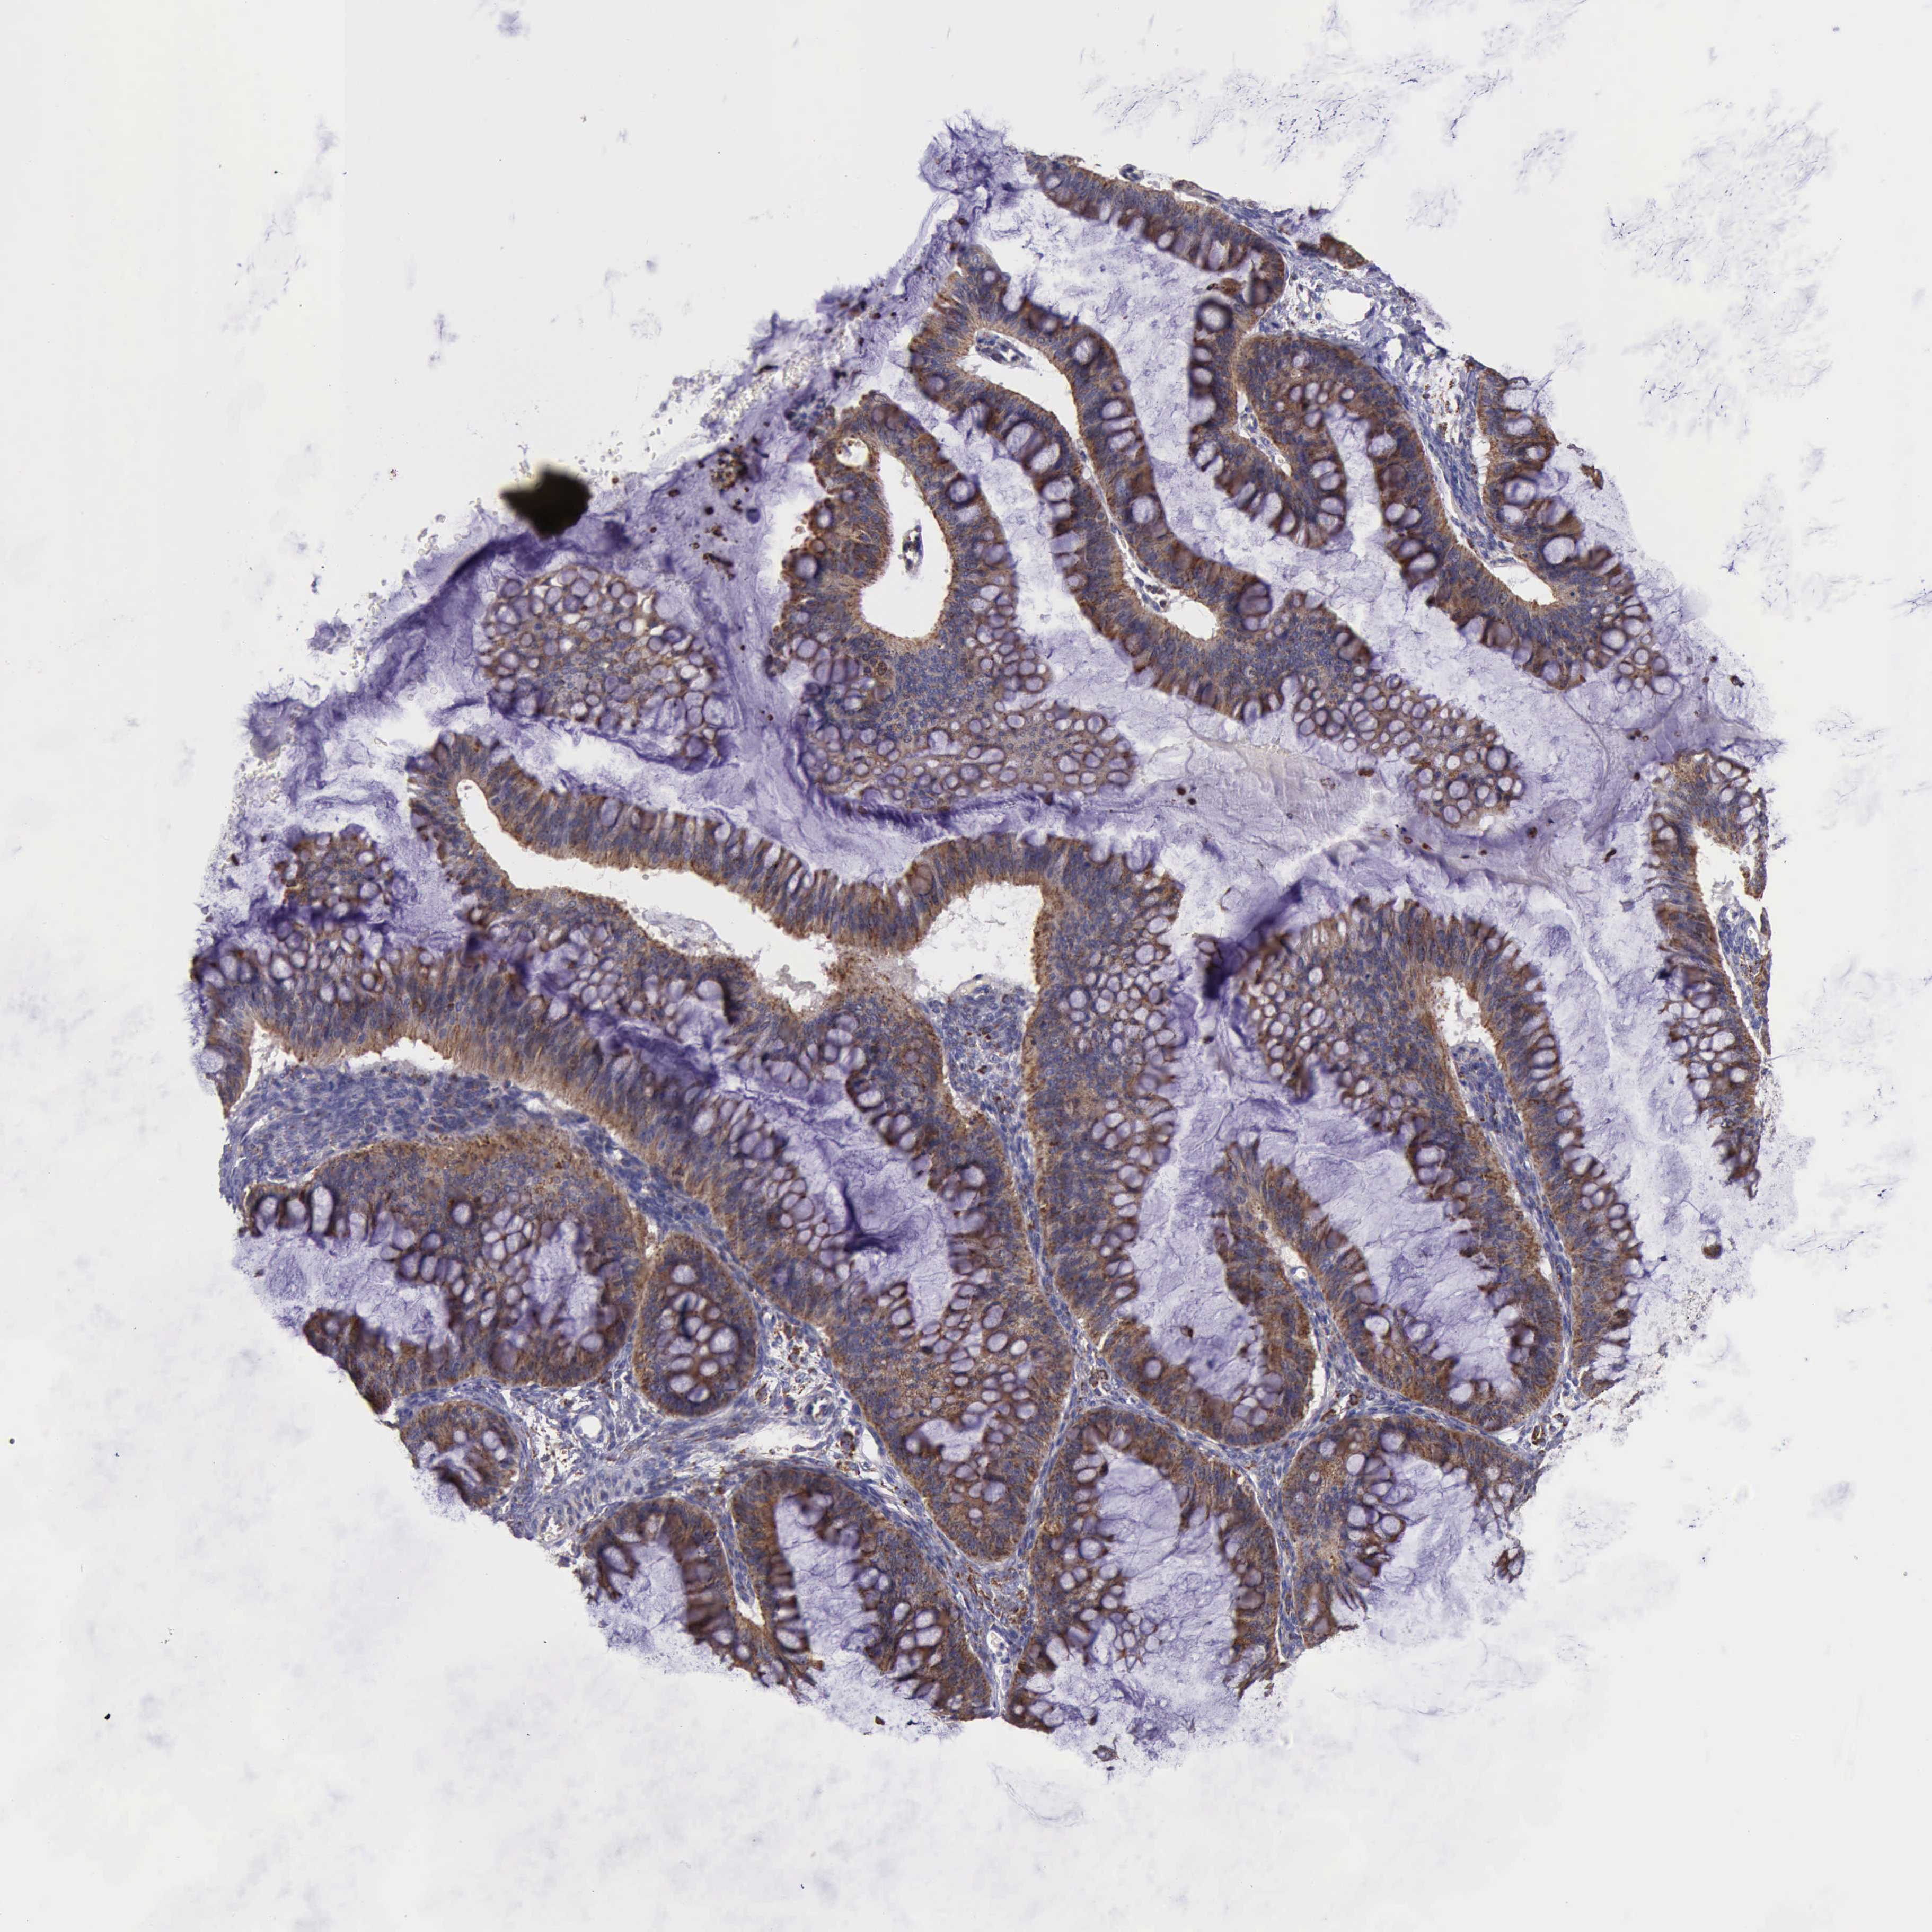

OVARIAN CANCER - Protein expressioni

A mouse-over function shows sample information and annotation data. Click on an image to view it in a full screen mode. Samples can be filtered based on level of antibody staining by selecting one or several of the following categories: high, medium, low and not detected. The assay and annotation is described here.

Note that samples used for immunohistochemistry by the Human Protein Atlas do not correspond to samples in the TCGA dataset.

Antibody stainingi

Antibody staining in the annotated cell types in the current human tissue is reported as not detected, low, medium, or high, based on conventional immunohistochemistry profiling in selected tissues. This score is based on the combination of the staining intensity and fraction of stained cells.

Each image is clickable and will lead to virtual microscopy that enables deeper exploration of all samples and also displays staining intensity scores, fraction scores and subcellular localization as well as patient and tissue information for each sample.

Antibody HPA000994

Cystadenocarcinoma, mucinous, NOS

Carcinoma, endometroid

Cystadenocarcinoma, serous, NOS

Carcinoma, NOS